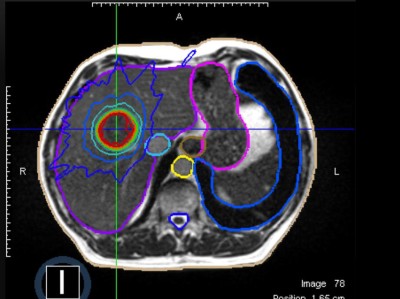

Wie gelingt eine erfolgreiche Stereotaxie bei Oligometastasierung?

Die Hochpräzisionsbestrahlung bzw. Stereotaxie spielt eine zentrale Rolle bei oligometastatischen Tumoren. Relevante technischen und prozeduralen Anforderungen wurden durch entsprechende Fachgesellschaften definiert. Darüber hinaus spielen moderne bildgebende Verfahren eine zentrale Rolle bei der Ausbreitungsdiagnostik, Zielvolumendefinition und Beurteilung des Therapieansprechens.

Chondroblastom in der MRT/© Camp L et al. / all rights reserved Springer Medizin Verlag GmbH, Patellafraktur/© K. Fehske · R. Hoffmann / all rights reserved Springer Medizin Verlag GmbH, Röntgenaufnahme eines nicht ossifizierenden Fibroms /© Weber M et al. / all rights reserved Springer Medizin Verlag GmbH, Cholesterolgranulom im MRT/© Frederik F/ all rights reserved Springer Medizin Verlag GmbH, pathologische distale Femurfraktur/© Omar M et al. / all rights reserved Springer Medizin Verlag GmbH, Frau unkenntlich fasst sich ans Knie/© Pornpak Khunatorn / Getty Images / iStock (Symbolbild mit Fotomodell), Echondrom/© Springer Medizin, Ausprägungen einer antiresorptivaassoziierten Kiefernekrose (AR-ONJ)/© Ristow, O. et al. / all rights reserved Springer Medizin Verlag GmbH, Stereotaktische Strahlentherapie (SBRT) einer solitären ossären Metastase in dem Brustwirbelkörper/© Springer Medizin Verlag GmbH, Arzt oder Pfleger schaut auf eine im MRT Eingang liegende Person/© [M] oksanazahray / stock.adobe.com (Symbolbild mit Fotomodell), Wirbelsäulenmetastase/© stockdevil / stock.adobe.com, Bluttransfusion/© Tobilander / Fotolia, Ärztin und kleines Mädchen mit Kopftuch/© FatCamera / Getty Images / iStock (Symbolbild mit Fotomodellen), Inhalt eines Fläschchens wird aufgezogen/© MarianVejcik / Getty Images / iStock, aneurysmatische Knochenzyste im Bereich des rechten distalen Femurs/© Springer Nature / all rights reserved Springer Medizin Verlag GmbH, Ewing-Sarkom/© Botos B. Z. et al. / all rights reserved Springer Medizin Verlag GmbH, Tumorkalzinose in der Hüfte/© Sukun A & Weber M.-A. , Computertomografie-gesteuerte periradikuläre Therapie auf Höhe von Lendenwirbelkörper 5/Sakralwirbelkörper 1 rechts/© Institut für Diagnostische und Interventionelle Radiologie des Klinikums St. Marien Amberg, Körperstereotaxie einer Lebermetastase im Segment VIII am MR-LINAC/© Ehret, F. et al. / all rights reserved Springer Medizin Verlag GmbH, Search Icon, Arthropedia, Ärzteteam führt Hüftoperation durch/© ATRPhoto / stock.adobe.com (Symbolbild mit Fotomodell), Gebrochener Fuß im Gips/© Aleksandr Kirillov / stock.adobe.com (Symbolbild mit Fotomodell)